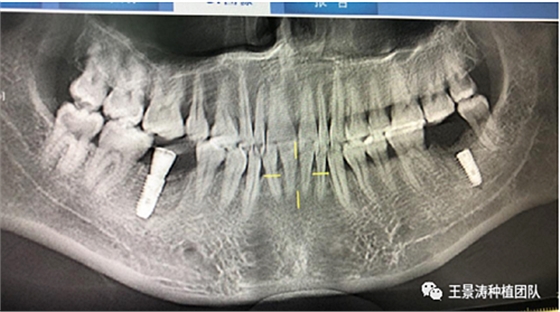

左側(cè)下頜第二磨牙及右側(cè)下頜第一磨牙同時(shí)即刻種植病例?;颊吣贻p女性,無系統(tǒng)性疾病。37及46殘冠及殘根,且46劈裂,無法冠修復(fù),必須拔除。37根尖慢性炎癥,大量肉芽組織存在,46根分叉較高,根分叉骨質(zhì)尚可。CBCT示:根尖骨質(zhì)至下牙槽神經(jīng)管距離可滿足種植體的初期穩(wěn)定性,遂考慮即刻種植,并在種植體周邊填入骨粉并覆蓋骨膜,雙側(cè)的種植體初期穩(wěn)定性相差無幾,但考慮到37根尖慢性炎癥較大,遂給予埋入式種植。

患者左側(cè)16慢性根尖周炎,17缺失。16根尖炎癥距上頜竇底較近,需內(nèi)提升,但是因?yàn)閮?nèi)提升后骨質(zhì)較薄所致植入深度過深,埋入式植入。17非埋入式種植。后期效果均可。